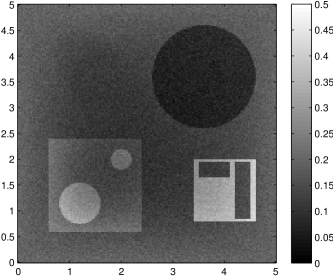

The edge detector is used to detect jumps in the derivatives of the data up to second order (to obtain an initial estimate of the parameter jump set ). Since this process is highly sensitive with respect to noise, we varied the edge detection procedure subject to the amount of noise in the data. In the noise-free examples, we estimated the jumps of all three functions , that is, jumps of derivatives of up to second order. We restricted the jump estimation to for the low-noise examples (i.e., jumps of derivatives up to first order) and in the high-noise examples (only jumps in the data itself).

Reconstruction results and error profiles at different noise levels can be seen in Figures 3 and 4. In both examples, the noise-free reconstructions are very accurate and contain mostly smoothing error. In the low-noise reconstructions, due to the fact that more regularization is necessary, some of the parameter variation is underestimated. In the high-noise examples, most detail in is lost since a lot of regularization is required to get reasonable results. The fine detail in can, however, still be recovered very accurately in both examples.